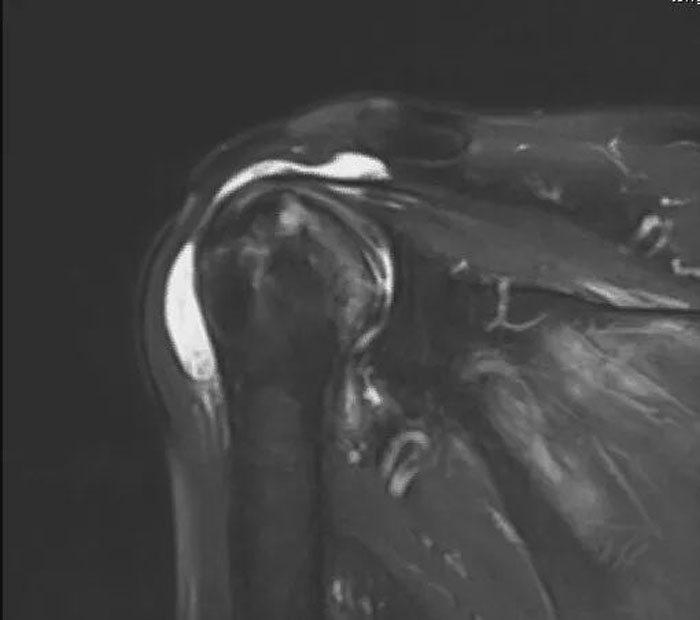

肩關節(jié)是人體所有關節(jié)中活動量最大、最靈活的一個關節(jié),任何損傷都會讓患者“飽受肩熬”。本例患者賀大爺肩關節(jié)疼痛數(shù)月,夜間疼痛嚴重,影響睡眠,肩關節(jié)活動明顯受限,行磁共振檢查提示肱骨頭壞死并肩袖損傷??盗⑿轮魅吾t(yī)師在考慮患者病情、影像學檢查、風險評估、術后獲益以及患者和家屬意愿的基礎上,建議患者行反式人工全肩關節(jié)置換術,重建患者肩關節(jié)。

術前